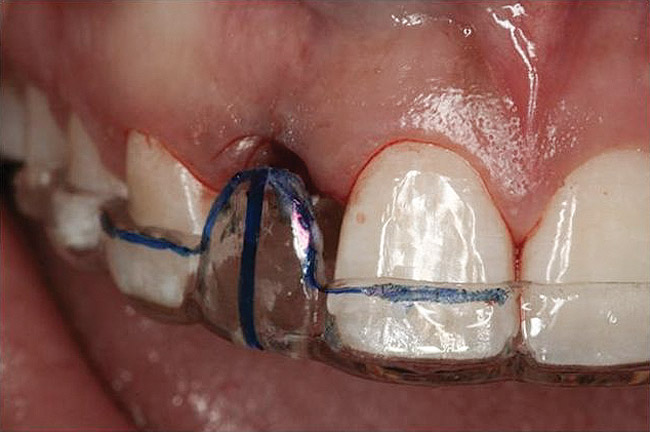

Figure 21   Gingival zenith planning: The location of the gingival zenith for this missing lateral incisor is not fully evident during initial clinical evaluation (Fig 21). Subsequent diagnostic waxing reveals the position of the planned gingival zenith (Fig 22). A thermoplastic template captures the position of the zenith and enables transferring this location to the clinical environment (Fig 23 and Fig 24). Final crown contours are defined by soft-tissue form (Fig 25).

Figure 21

Figure 22  Gingival zenith planning: The location of the gingival zenith for this missing lateral incisor is not fully evident during initial clinical evaluation (Fig 21). Subsequent diagnostic waxing reveals the position of the planned gingival zenith (Fig 22). A thermoplastic template captures the position of the zenith and enables transferring this location to the clinical environment (Fig 23 and Fig 24). Final crown contours are defined by soft-tissue form (Fig 25).

Figure 22

Figure 23  Gingival zenith planning: The location of the gingival zenith for this missing lateral incisor is not fully evident during initial clinical evaluation (Fig 21). Subsequent diagnostic waxing reveals the position of the planned gingival zenith (Fig 22). A thermoplastic template captures the position of the zenith and enables transferring this location to the clinical environment (Fig 23 and Fig 24). Final crown contours are defined by soft-tissue form (Fig 25).

Figure 23

Figure 24  Gingival zenith planning: The location of the gingival zenith for this missing lateral incisor is not fully evident during initial clinical evaluation (Fig 21). Subsequent diagnostic waxing reveals the position of the planned gingival zenith (Fig 22). A thermoplastic template captures the position of the zenith and enables transferring this location to the clinical environment (Fig 23 and Fig 24). Final crown contours are defined by soft-tissue form (Fig 25).

Figure 24

Figure 25  Gingival zenith planning: The location of the gingival zenith for this missing lateral incisor is not fully evident during initial clinical evaluation (Fig 21). Subsequent diagnostic waxing reveals the position of the planned gingival zenith (Fig 22). A thermoplastic template captures the position of the zenith and enables transferring this location to the clinical environment (Fig 23 and Fig 24). Final crown contours are defined by soft-tissue form (Fig 25).

Figure 25